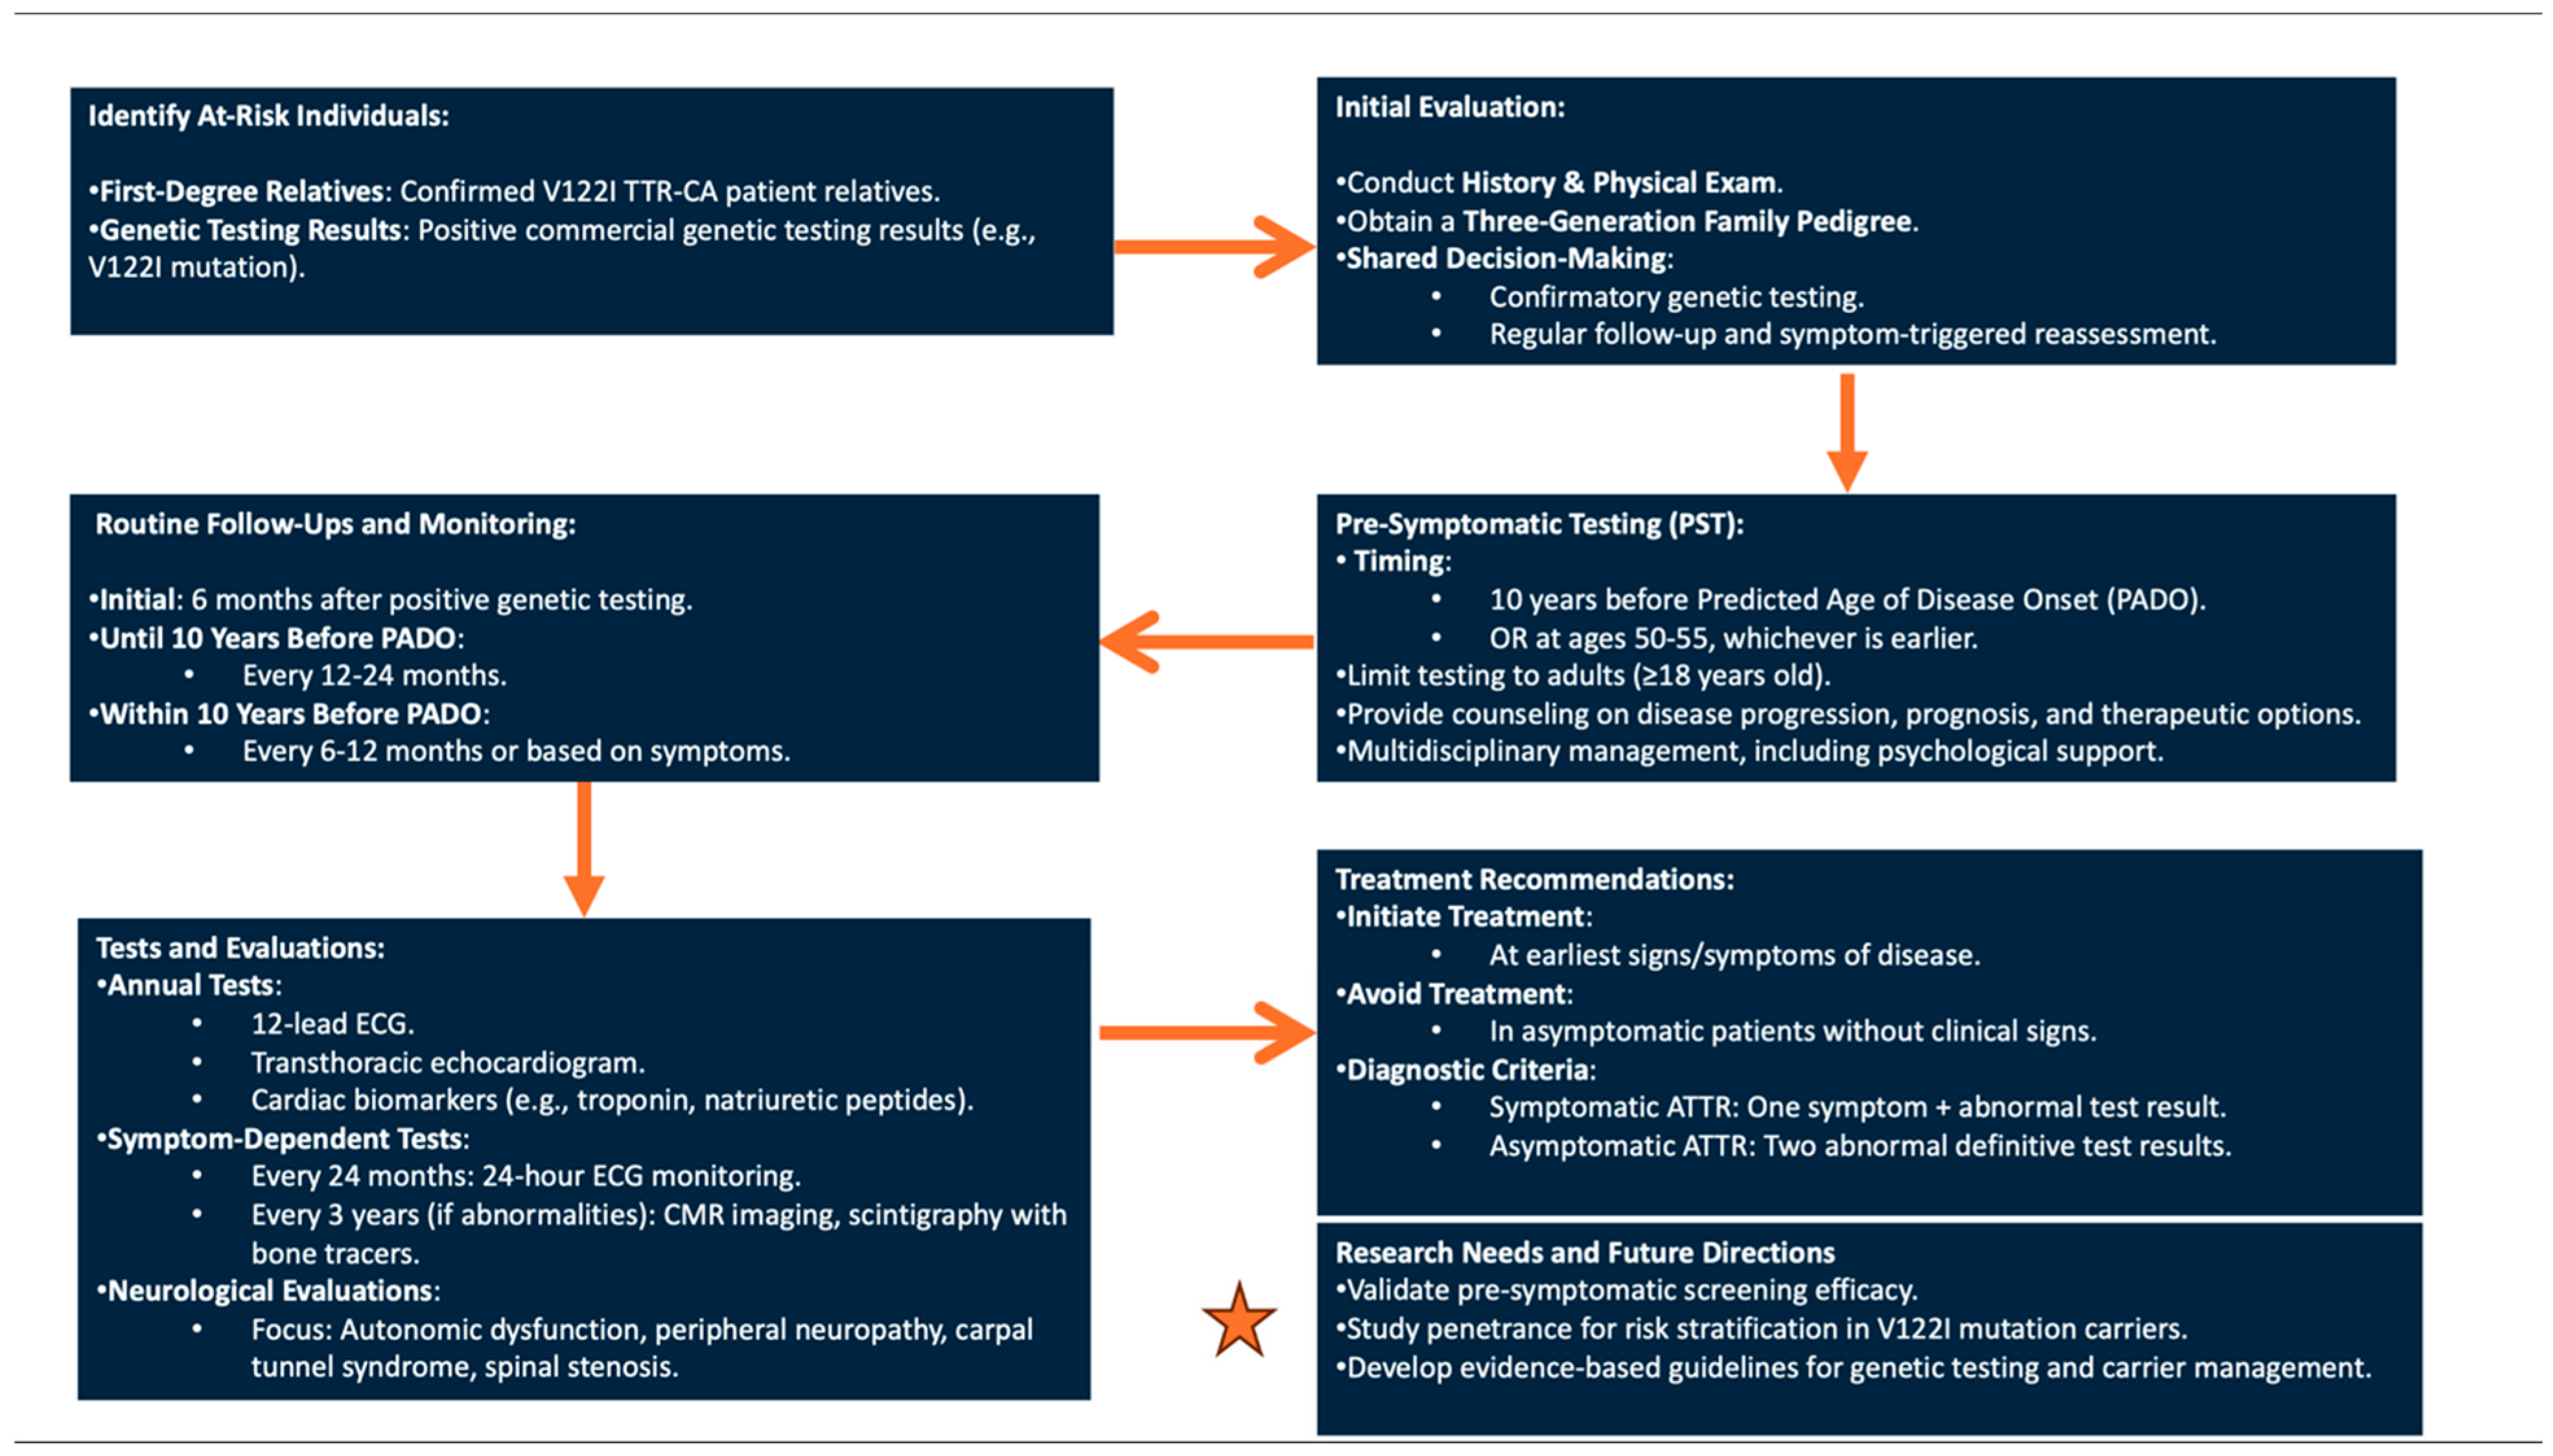

3. V122I TTR-CA: Pre-Symptomatic Genetic Testing Protocol and Management of Asymptomatic Carriers

4. Conclusions